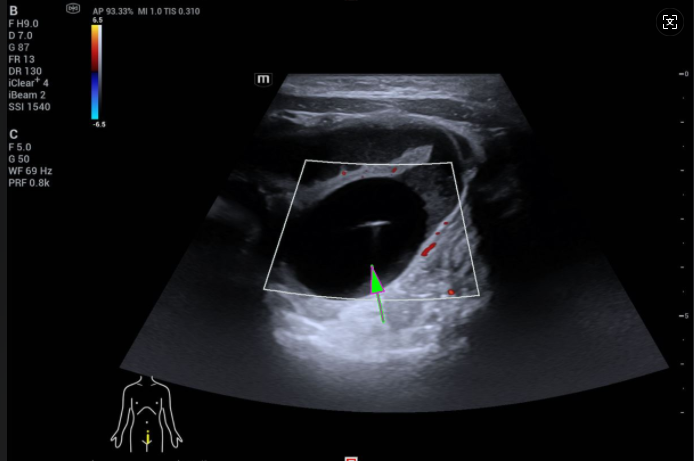

CT显示,小玥的小肠上段有明显扩张的情况,远端则是正常的干瘪状;而B超则显示,她的腹腔内有一个3.0×2.5cm的球状物。